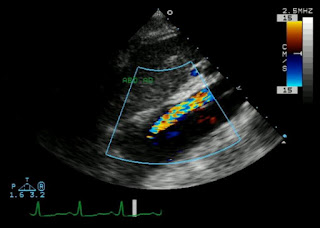

A 70 year old smoker with hypertension, hyperlipidemia, diabetes, peripheral vascular disease s/p femoral-femoral bypass, coronary artery disease s/p 4 vessel CABG presents with recurrent episodes of abdominal pain. The pain is dull, crampy, epigastric, usually beginning within an hour after eating, lasting about two hours. He has tried famotidine and pantoprazole without any relief. It is worse with ice cream, french fries, and fried chicken. Review of systems notes nausea, vomiting, early satiety, and weight loss. The patient is worried about cancer. Exam reveals a cachectic man with an abdominal bruit, but is otherwise unremarkable. There is no tenderness or pain to palpation. Routine laboratory tests, chest and abdominal radiographs, endoscopy, and colonoscopy are all negative. Lateral angiogram and angiogram with contrast injected into the inferior mesenteric artery are shown below.

Challenge: What's your diagnosis?